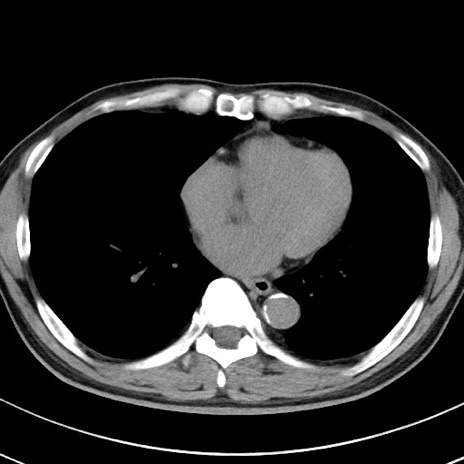

【腹部TIPS】症例29 参考症例 CT(横断像)

症例

70歳代男性